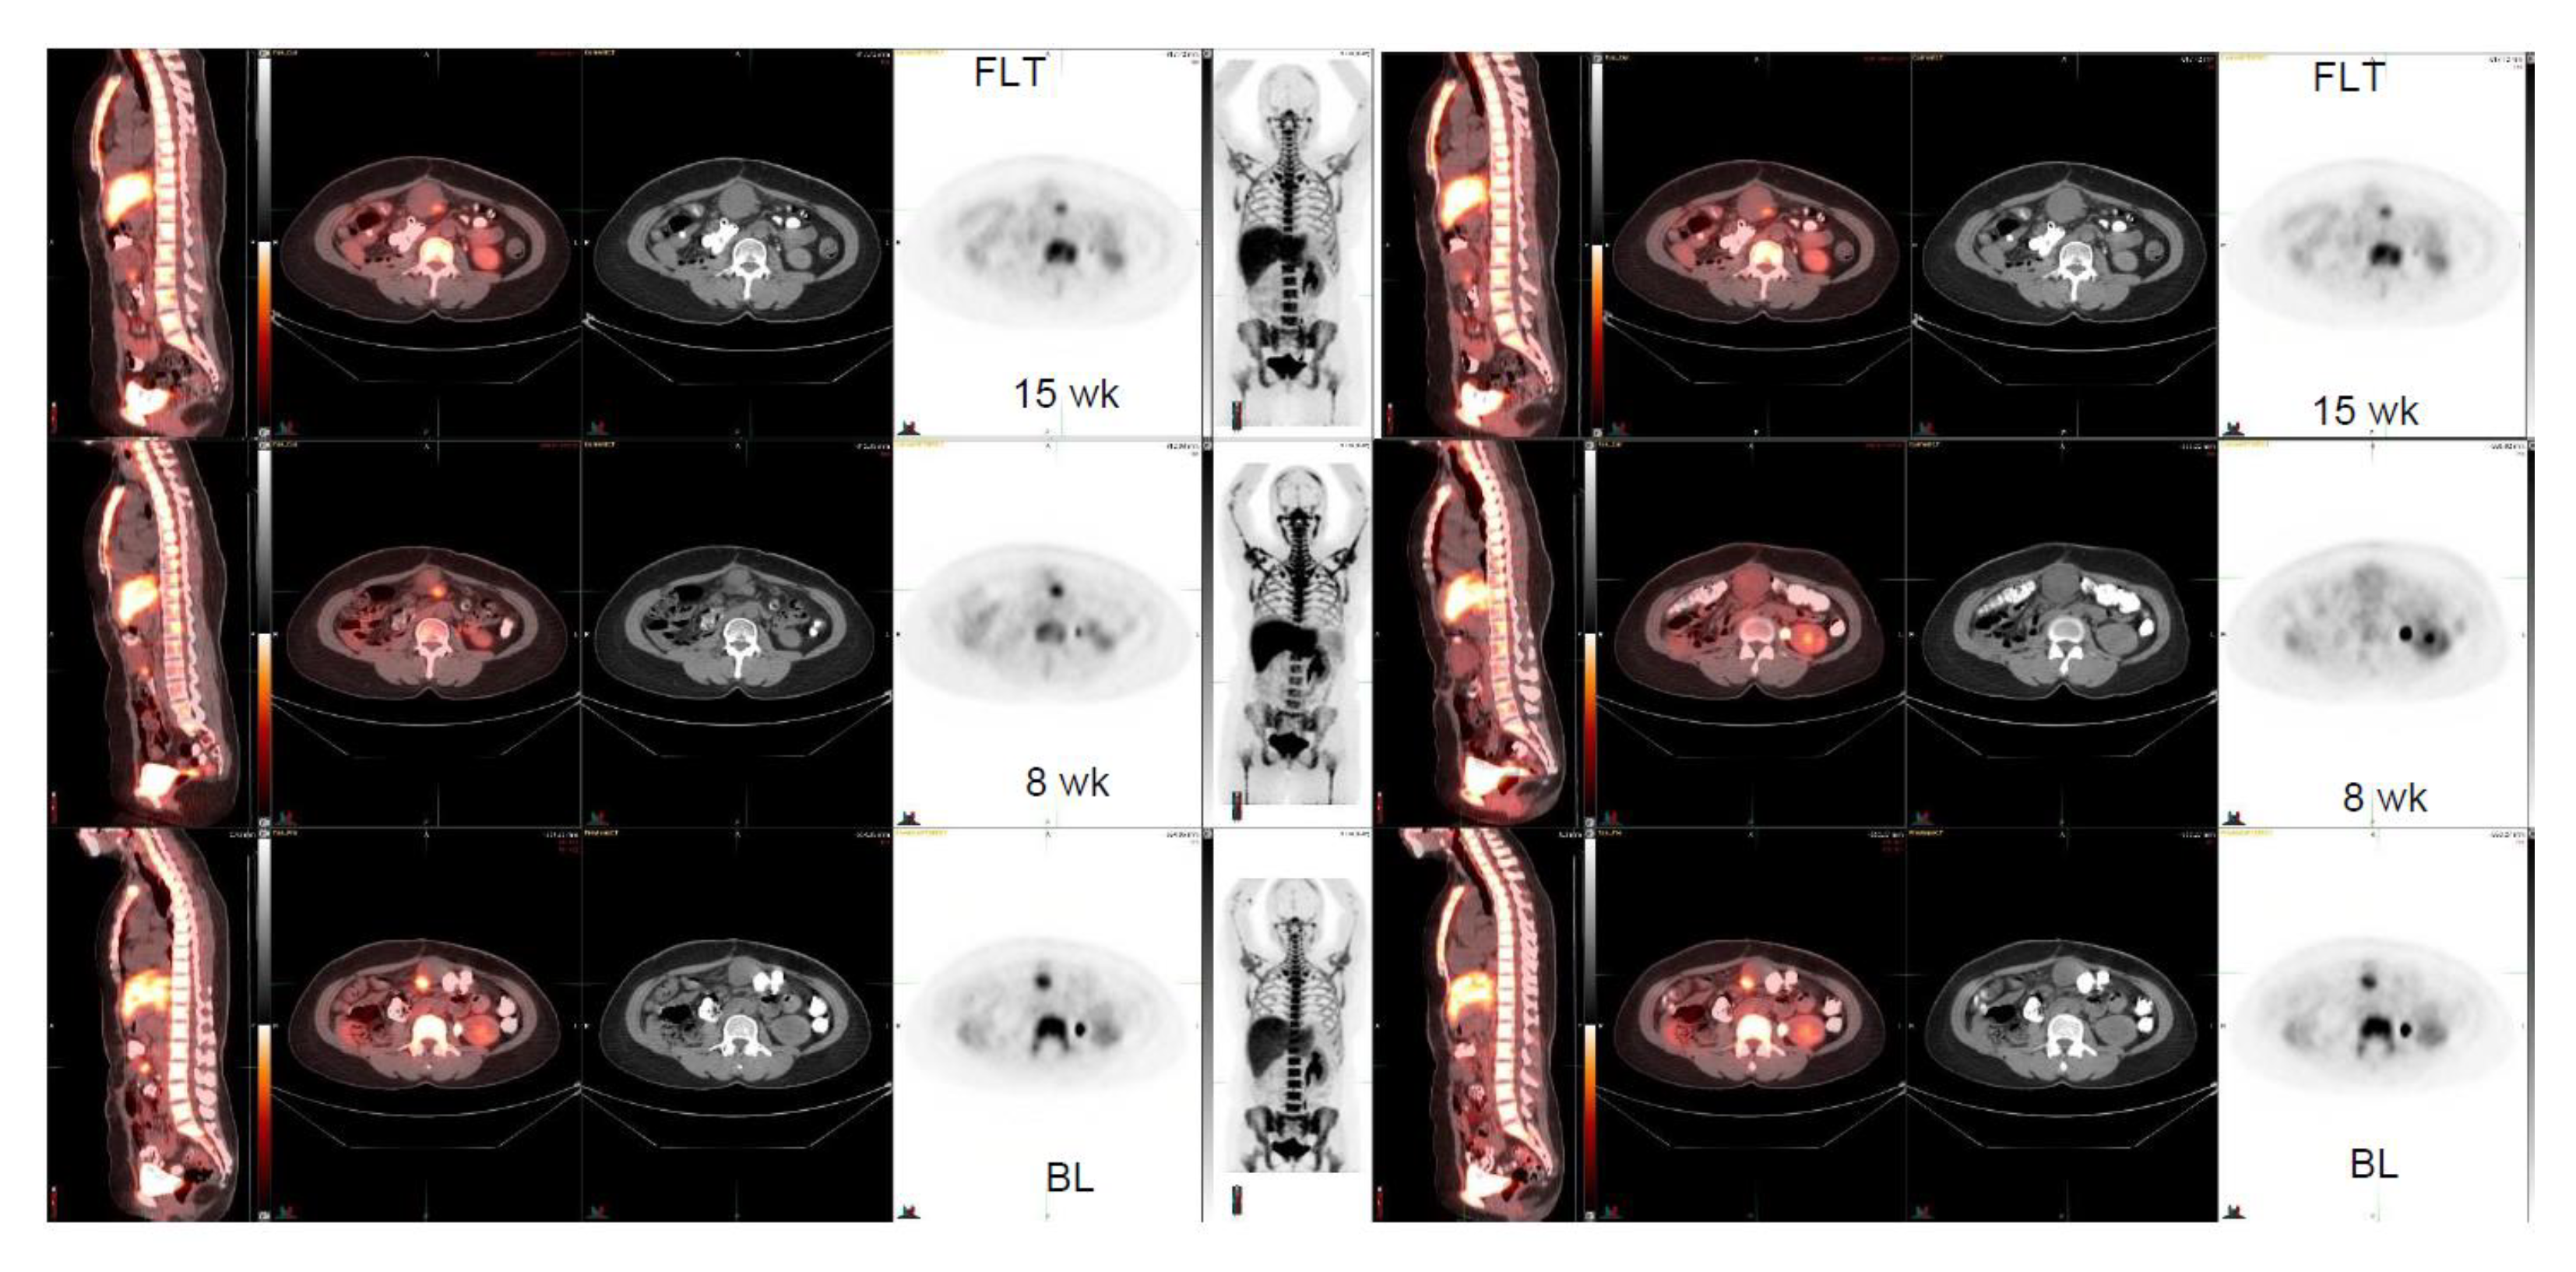

Four patient cases are shown (Figure 1, Figure 2, Figure 3 and Figure 4). A patient with GNET-tumor was studied at baseline and then subsequently at 1, 7, and 15 weeks with 18F-FLT. In addition, the patient also had 18F-FDG-PET imaging study at baseline and at 7 and 15 weeks (Figure 1). This patient had two mesenteric lymph node metastases (annotated R (right) and L(left)); with 18F-FLT, the outcome at seven weeks was -25% (R) and +7% (L), whereas 18F-FDG did not show any response (+19% (R) and +21% (L)). Later, at 15 weeks, the response was clear for 18F-FLT, with a change of −38% (R) and −38% (L), whereas 18F-FDG did not show any clear response (−18% (R) and −2% (L)). A patient with liposarcoma is shown in Figure 2 demonstrating anterior peritoneal mass with three connecting compartments. The patient was studied at baseline and at 1, 8, and 15 weeks with 18F-FLT. FLT-uptakes decreased in the most active site as follows: SUVmax 5.8→4.2 (−28%) →3.5 (−40%). The biggest tumor actually increased in size on CT as follows: 4.1 cm × 3.2 cm →5.5 cm × 4.1 cm→5.6cm × 5.2 cm (Figure 2).

Figure 2.

Liposarcoma. FLT-study at baseline, at 8, and at 15 weeks (3 rows). Anterior peritoneal mass is seen; the tumor consists of three components, which are in connection. The biggest tumor changes on CT as follows: 4.1 cm × 3.2 cm ->5.5 cm × 4.1 cm->5.6cm × 5.2 cm. FLT-uptakes changes in the most active site as follows: SUVmax 5.8 ->4.2 -> 3.5.

FLT PET should always be used as a follow-up of a new therapy for comparison with baseline. A single study may be beneficial only for staging of aggressive tumors with high uptakes. We also observed that intra- and intertumoral heterogeneity could be visualized using FLT, such as in Figure 2. There is a trend of sex difference showing that females’ response is more pronounced than males. However, given the heterogeneity of the tumors, heterogeneity of therapy, different therapies in different dose levels, low number of patients, and the power, it may be premature to make observations or any conclusions based on this data.